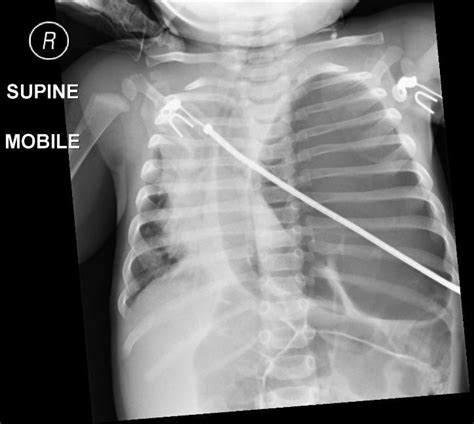

Initially, the focus is on "gentle ventilation." Medical teams avoid aggressive breathing machines that might further damage the sensitive, underdeveloped lungs. In severe cases, infants may be placed on ECMO (Extracorporeal Membrane Oxygenation), a life-support system that does the work of the heart and lungs, allowing the infant’s own systems to stabilize.

Once the infant is stable—often several days or weeks after birth—a pediatric surgeon performs a repair. The surgeon gently moves the displaced abdominal organs back into their proper place in the abdomen and closes the hole in the diaphragm. If the hole is small, it is stitched together; if the hole is large, a prosthetic patch may be used to create a solid barrier.

The severity of CDH is largely determined by the timing of the defect during gestation and the specific organs that migrate into the chest. In many cases, the heart may also be pushed out of its normal position, which can further impact circulatory function at birth. This combination of underdeveloped lungs and potential circulatory strain is why babies born with CDH require specialized neonatal care immediately upon delivery.